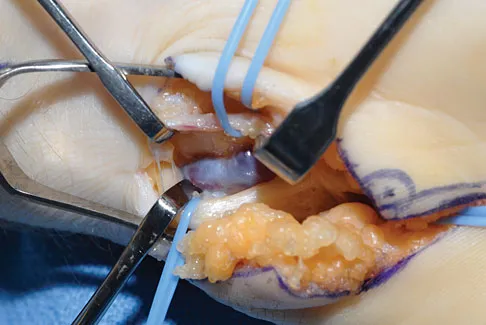

A 40-year-old man has a painful mass on his anterior ankle joint with limited range of motion. A radiograph, MRI scan, a gross specimen, and a hematoxylin/eosin biopsy specimen are shown in Figures 5a through 5d. What is the most likely diagnosis?

Explanation

Synovial chondromatosis results from chondroid metaplasia within the synovium. Male to female ratio is 2:1, with a peak incidence in early adult life. Radiographs can show speckled cal